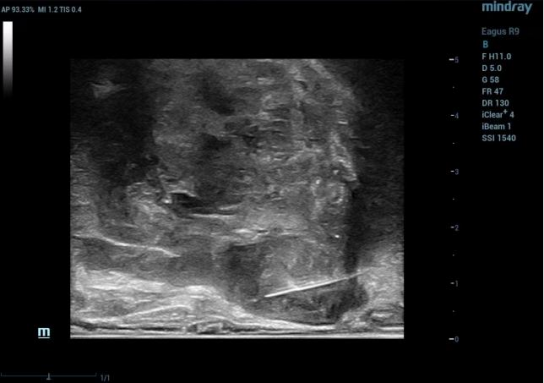

(图3为双平面探头下前列腺对应区域可疑结节的高频声像;图4为高频声像下该区域的活检)

超声引导下经会阴前列腺穿刺活检术就是在患者会阴部局部麻醉的情况下,经直肠超声定位,在会阴部入针进行前列腺穿刺,收集组织标本送检,最后消毒加压包扎会阴部进针点。

术中会将前列腺分为10个区域,在直肠超声实时双平面引导下,用仅直径1.2mm细针在前列腺组织内提取组织。